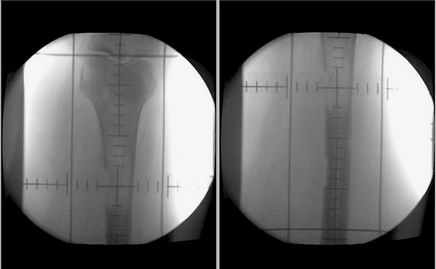

Ke snížení procenta komplikací je dnes nutné využít 3D plánování pomocí CT vyšetření a označení všech kritických orgánů

– jater, kontralaterální ledviny, míchy apod. Velmi důležitá je definice cílového objemu, vhodné je využití chirurgických klipů označujících lůžko ledviny. Samozřejmostí je rovněž výpočet objemové dávky jednotlivých orgánů (histogram dávka/objem). Tím významně eliminujeme procento komplikací radioterapie, kterým byly zatíženy historické studie. Stein a spol. uvádí snížení komplikací u skupiny 56 pacientů léčených pooperační radioterapií v dávce 46 Gy na 5 % (pouze u 3 pacientů z celkového počtu 56 nemocných).